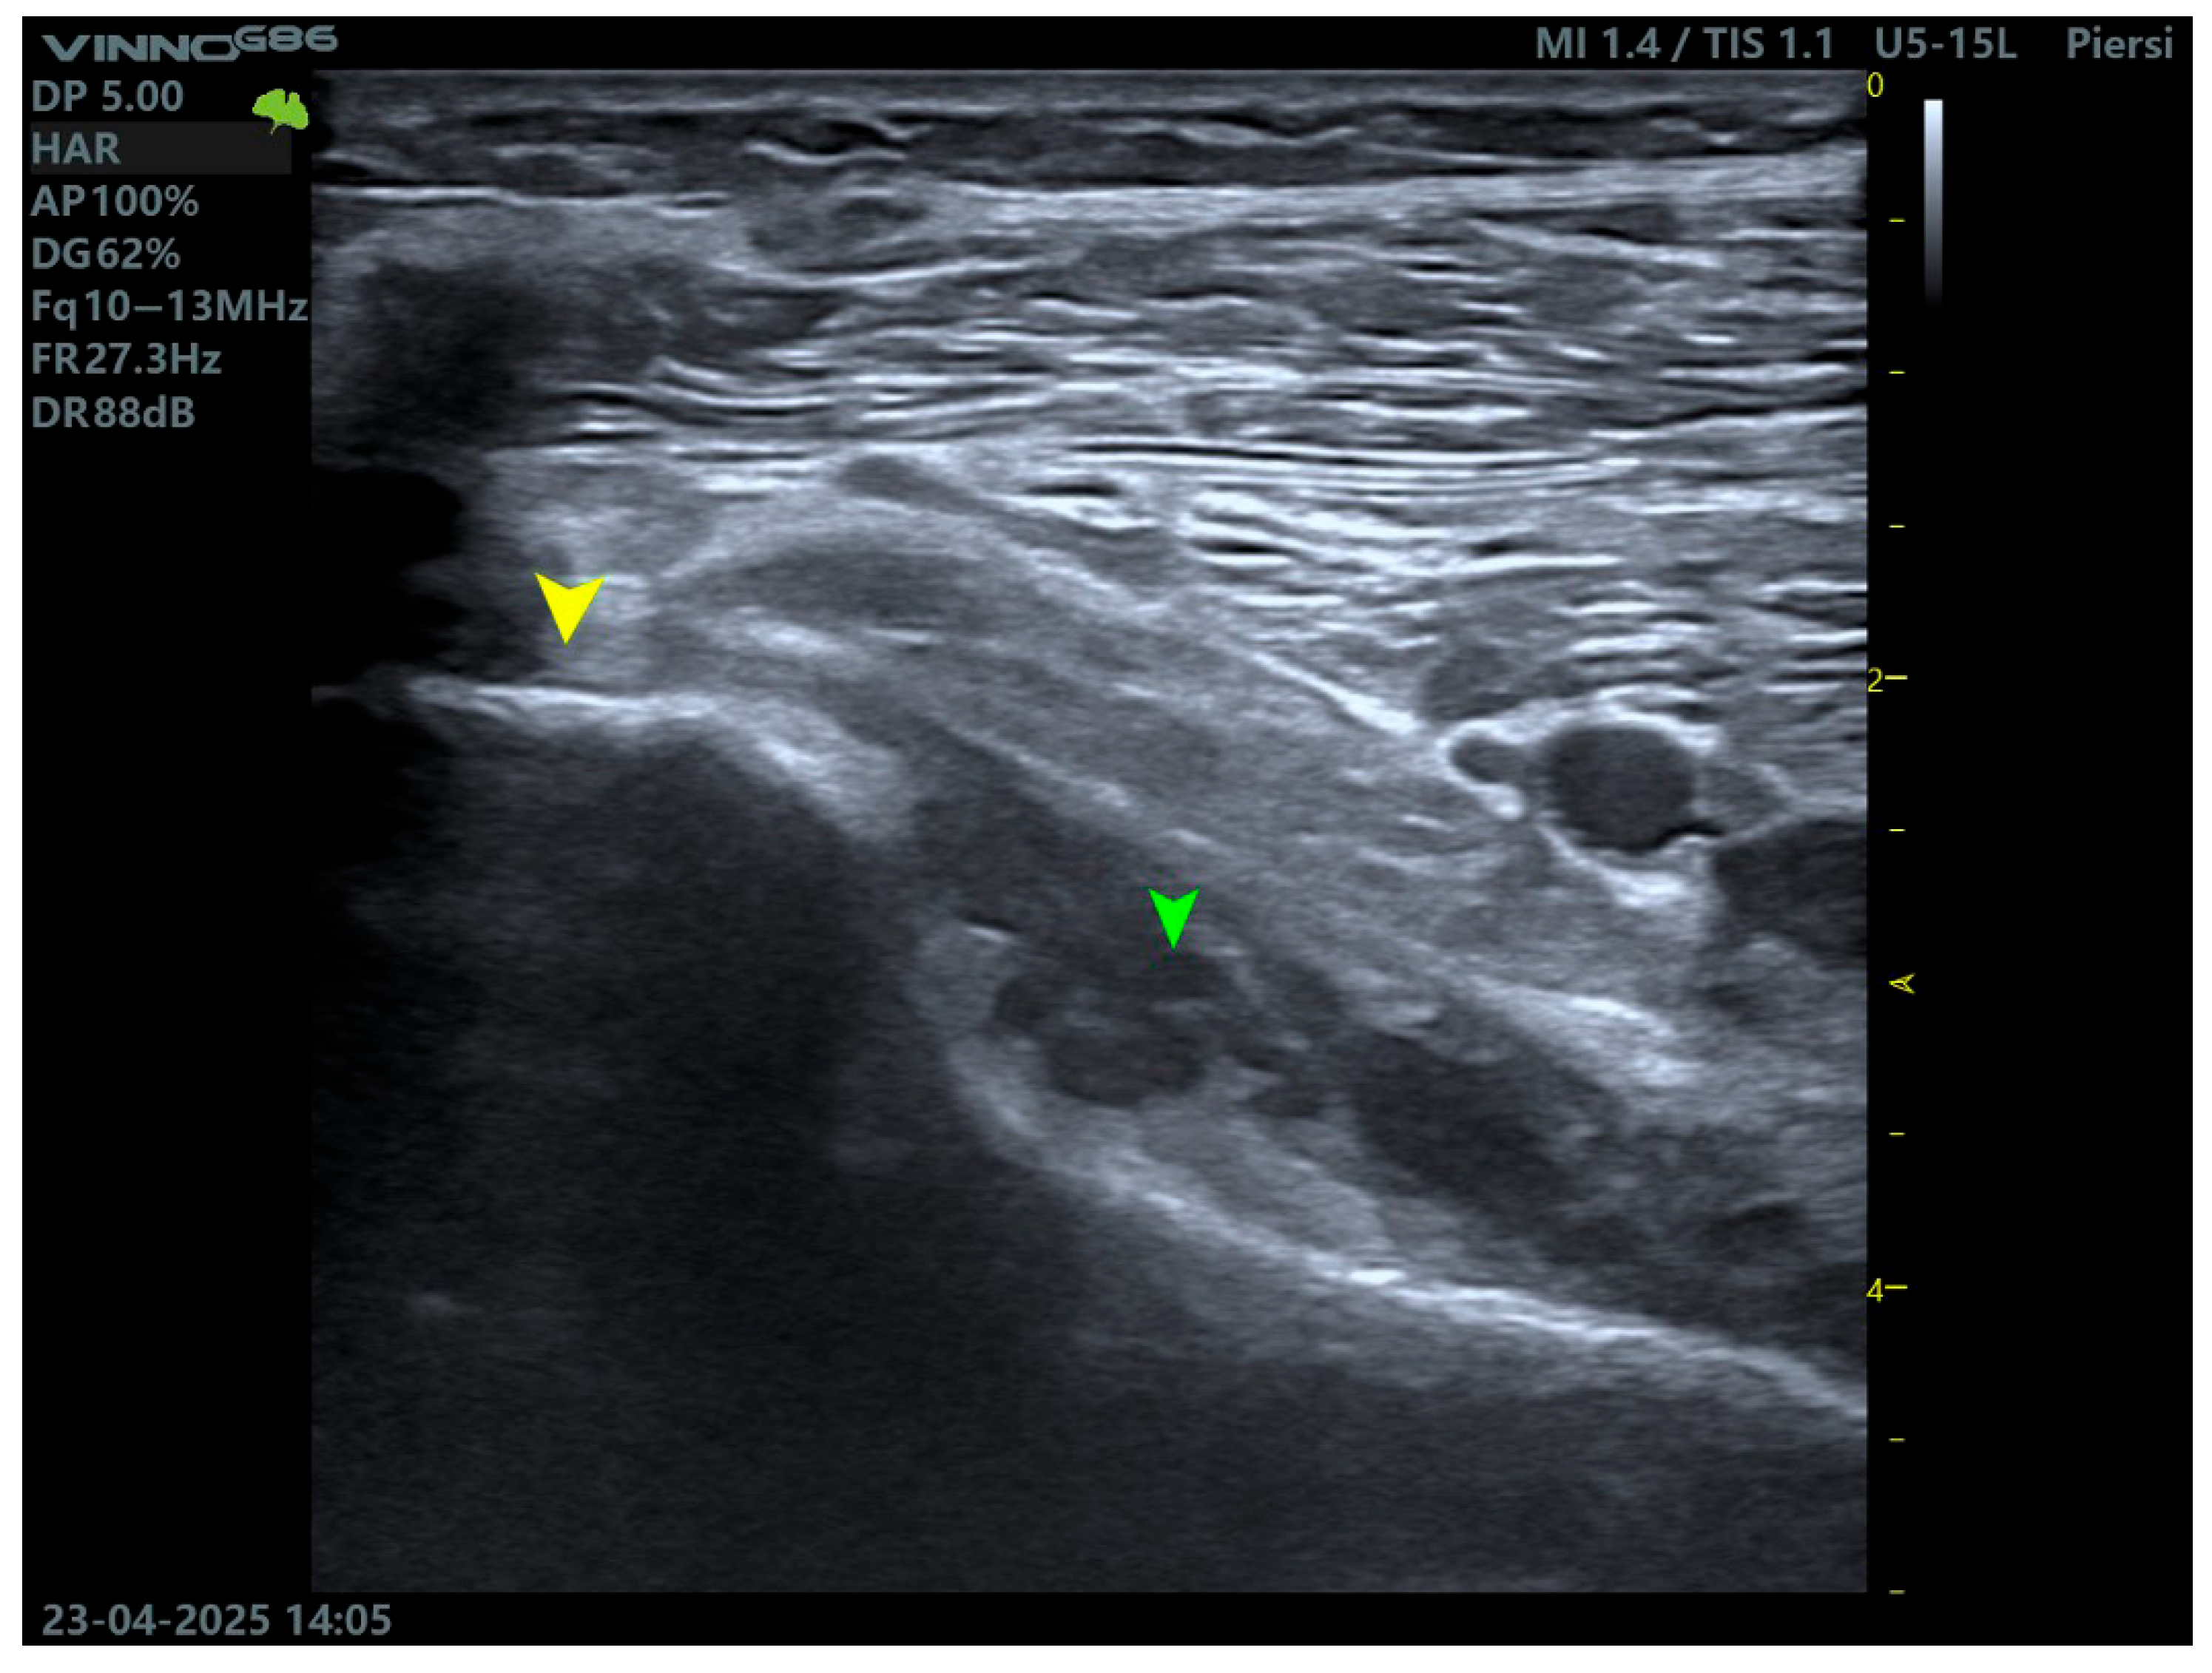

5.3. High-Resolution Ultrasound (US)

High frequency ultrasonography (≥12 MHz) is gaining relevance as a rapid, dynamic, and non-invasive tool for PT assessment, particularly in outpatient or sports medicine settings [18]. Scanning is performed with the patient in the prone position or with the knee flexed to 30–45°, while applying internal and external tibial rotation. This facilitates the dynamic observation of tendon gliding relative to the adjacent structures and detection of the accessory bands—Figure 3.

Figure 3.

Ultrasound imaging of the popliteus muscle. The yellow arrow indicates the tendon, while the green arrow indicates the muscle belly.

An ultrasound enables the evaluation of tendon echotexture, integrity, calcifications, enthesopathy, and peritendinous fluid collections. It is especially useful in the assessment of lateral knee pain following trauma, particularly in cases where MRI is unavailable or contraindicated (e.g., due to metallic implants) [2].